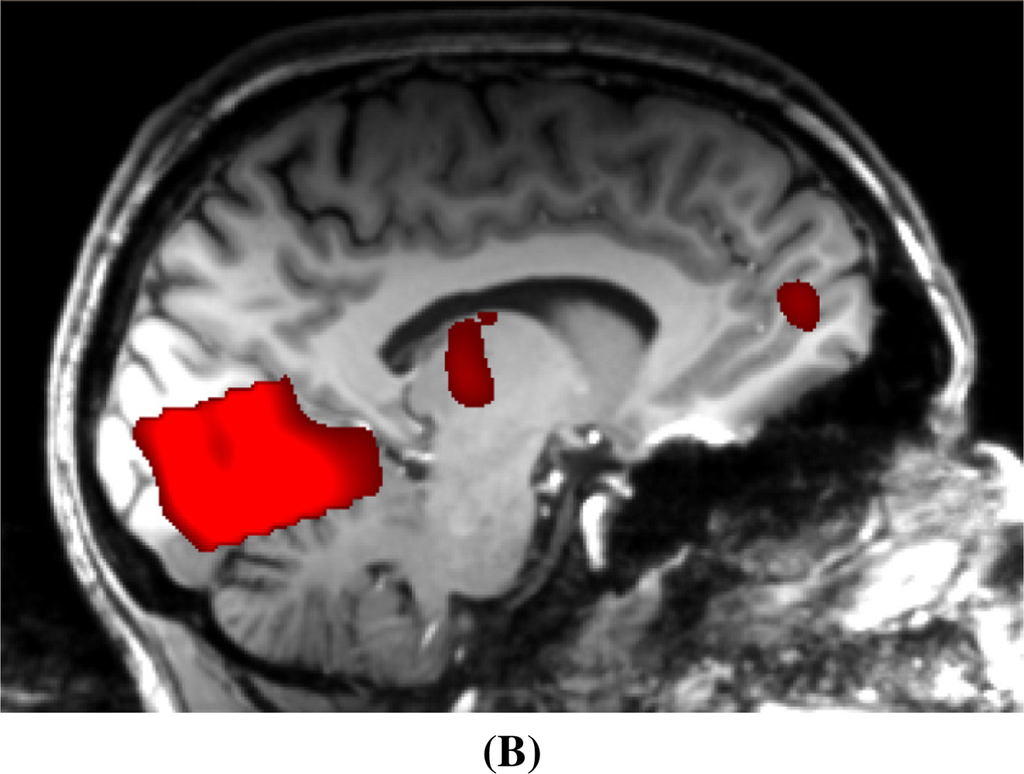

2.2. Functional MRI

2.3. Multi-Modal Integration of MRI, fMRI, and Slow Cortical Potentials (SCP, DC-EEG)

Functional brain imaging: